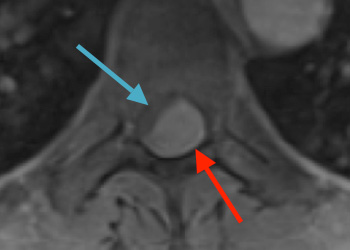

Preoperative MRI T1w demonstrating a large enhancing tumor (red arrow) causing severe cord compression and displacement (blue arrow)

Preoperative MRI T2 demonstrating obstruction of CSF around the cord (blue arrow), resulting from the tumor (red arrow)